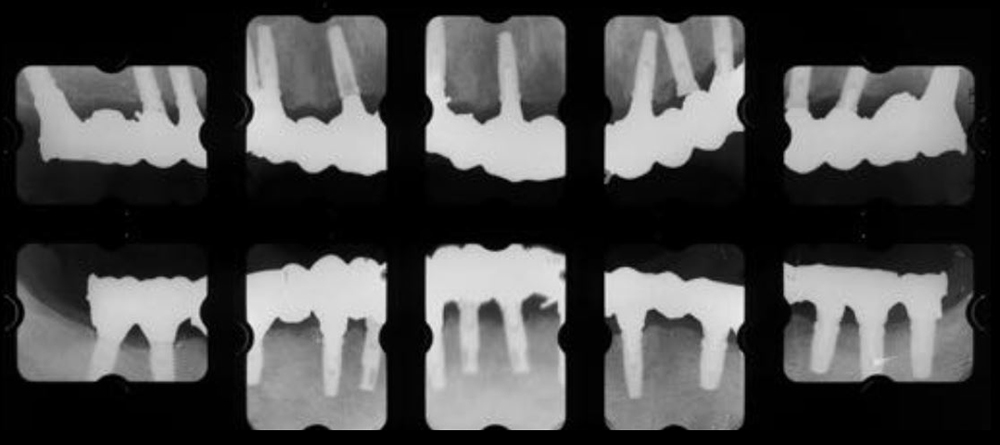

治療前01

治療前02

治療前03